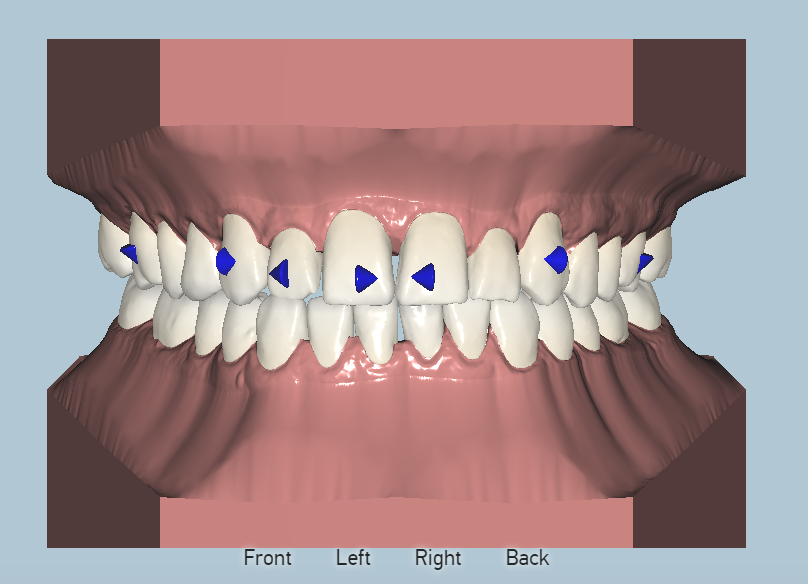

Orthodontist Proposal

After all materials are gathered, an orthodontist creates the movement proposal for the doctors approval. This is done through an on-line link that can be viewed in each stage of the process in 3D. Changes can be requested as needed or the proposal is approved for production.

Placeholder Picture